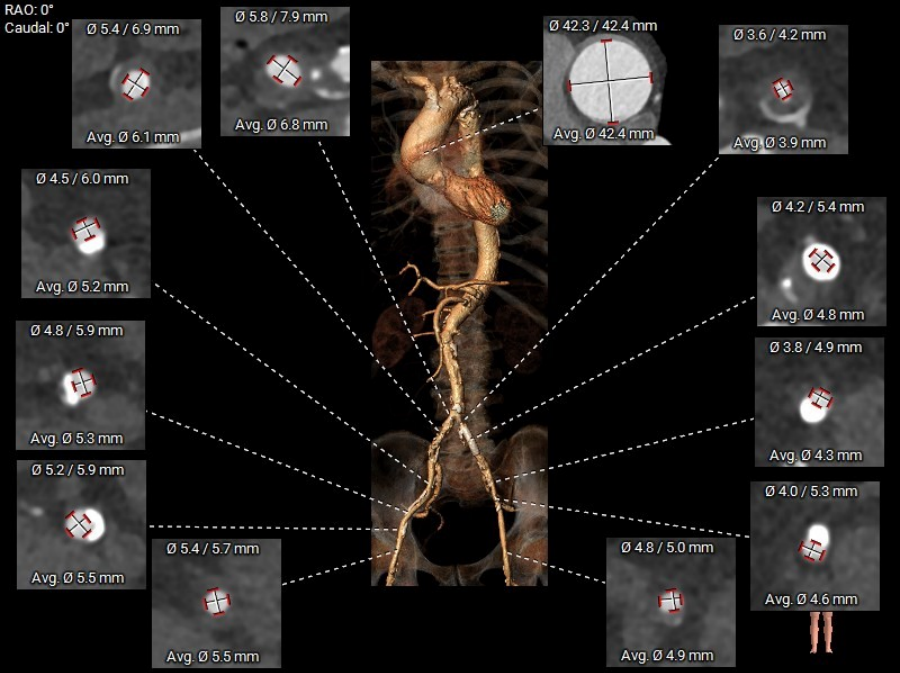

CT评估-外周测量:双侧入路偏细,左侧入路小于5.0mm,右侧髂外段入路最小约5.3mm,见三段长条钙化,考虑输送系统通过难度极大;锐角弓约64°,弓部到髂股动脉钙化较多,股动脉分叉皆位于股骨头以下